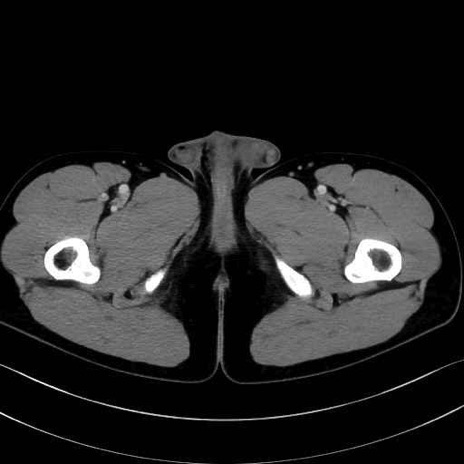

5. 大腿前面(大腿四頭筋群・伸筋群)

縫工筋 (Sartorius)

大腿直筋 (Rectus femoris)

外側広筋 (Vastus lateralis)

中間広筋 (Vastus intermedius)

6. 大腿内側(内転筋群)

恥骨筋 (Pectineus)

長内転筋 (Adductor longus)

短内転筋 (Adductor brevis)

大内転筋・小内転筋 (Adductor magnus / Adductor minimus)